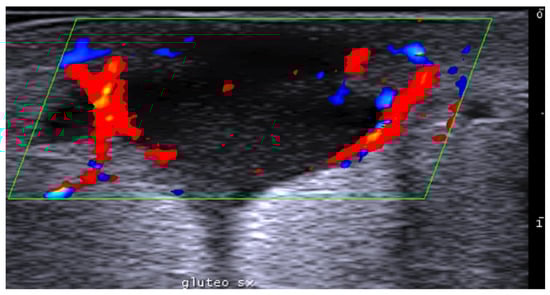

- Del Vecchio, D.; Kenkel, J.M. Practice Advisory on Gluteal Fat Grafting. Aesthetic Surg. J. 2022, 42, 1019–1029. [Google Scholar] [CrossRef]

- Vidal-Laureano, N.; Huerta, C.T.; Perez, E.A.; Earle, S.A. Augmented Safety Profile of Ultrasound-Guided Gluteal Fat Transfer: Retrospective Study with 1815 Patients. Aesthetic Surg. J. 2024, 44, NP263–NP270. [Google Scholar] [CrossRef] [PubMed]

- Elsaftawy, A.; Ostrowski, P.; Bonczar, M.; Stolarski, M.; Gabryszuk, K.; Bonczar, T. Buttock Augmentation with Ultrasonic Liposuction and Ultrasound-Guided Fat Grafting: A Retrospective Analysis Based on 185 Patients. J. Clin. Med. 2024, 13, 1526. [Google Scholar] [CrossRef]

- Elsaftawy, A.; Ostrowski, P.; Bonczar, M.; Stolarski, M.; Gabryszuk, K.; Bonczar, T. Enhancing Buttock Contours: A Safer Approach to Gluteal Augmentation with Ultrasonic Liposuction, Submuscular Implants, and Ultrasound-Guided Fat Grafting. J. Clin. Med. 2024, 13, 2856. [Google Scholar] [CrossRef]

- Wang, B.; He, P.; Zhao, R. B-ultrasound-assisted gluteal fat grafting in Asians: A prospective study of quantitative results from three-dimensional imaging and B-ultrasound analysis. J. Plast. Reconstr. Aesthetic Surg. 2024, 94, 12–19. [Google Scholar] [CrossRef] [PubMed]